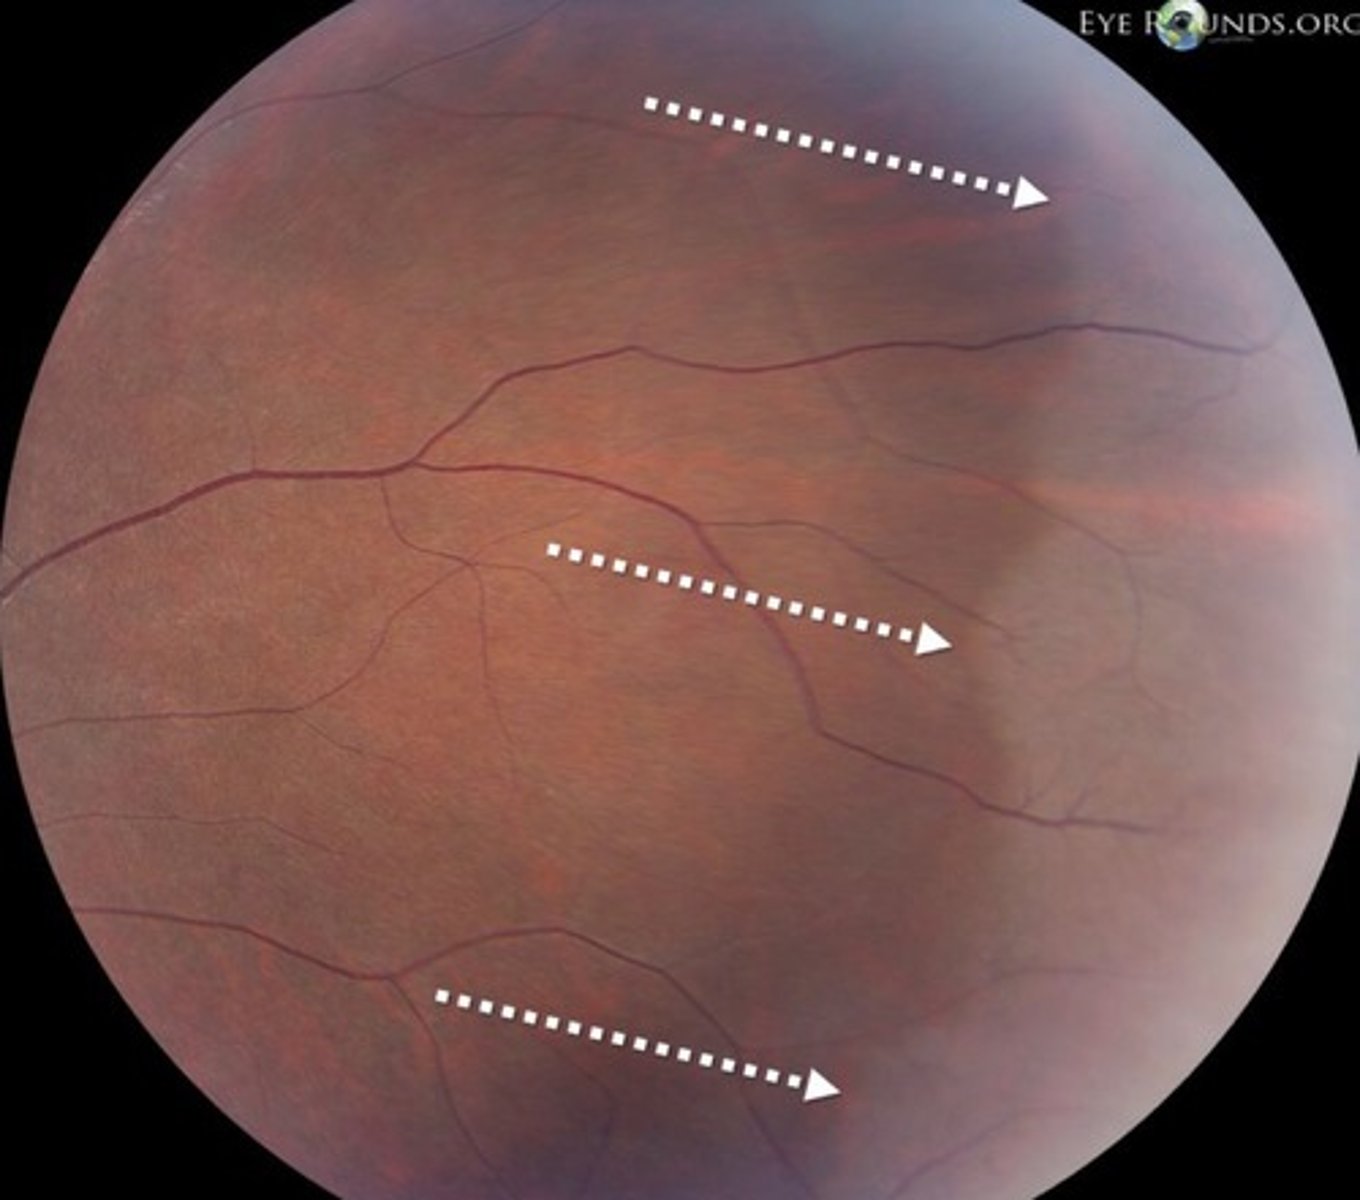

Pavingstone degeneration: aetiology

Occurs in about 30% of all patients

• Peripheral retinal degeneration

• Small, pale, non-elevated, depigmented areas

• Usually bilateral, mostly seen inferiorly

• Choroidal vessels seen due to RPE and outer retina loss

• May increase with age

• Benign

• Differentiate from chorioretinal scars, retinal holes, lattice degeneration